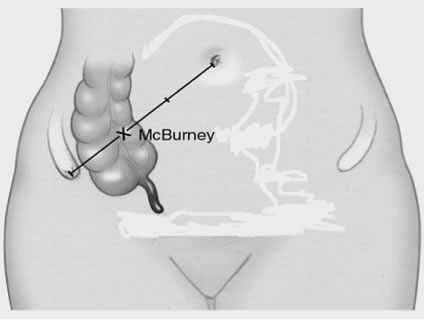

Στην «ανοικτή» σκωληκοειδεκτομή γίνεται λοξή τομή στο σημείο McBurney, ο έξω και έσω λοξός μυς διασχίζονται, χωρίς να διατέμνονται, το περιτόναιο διανοίγεται και ανευρίσκεται το τυφλό.

Σημείο McBurney